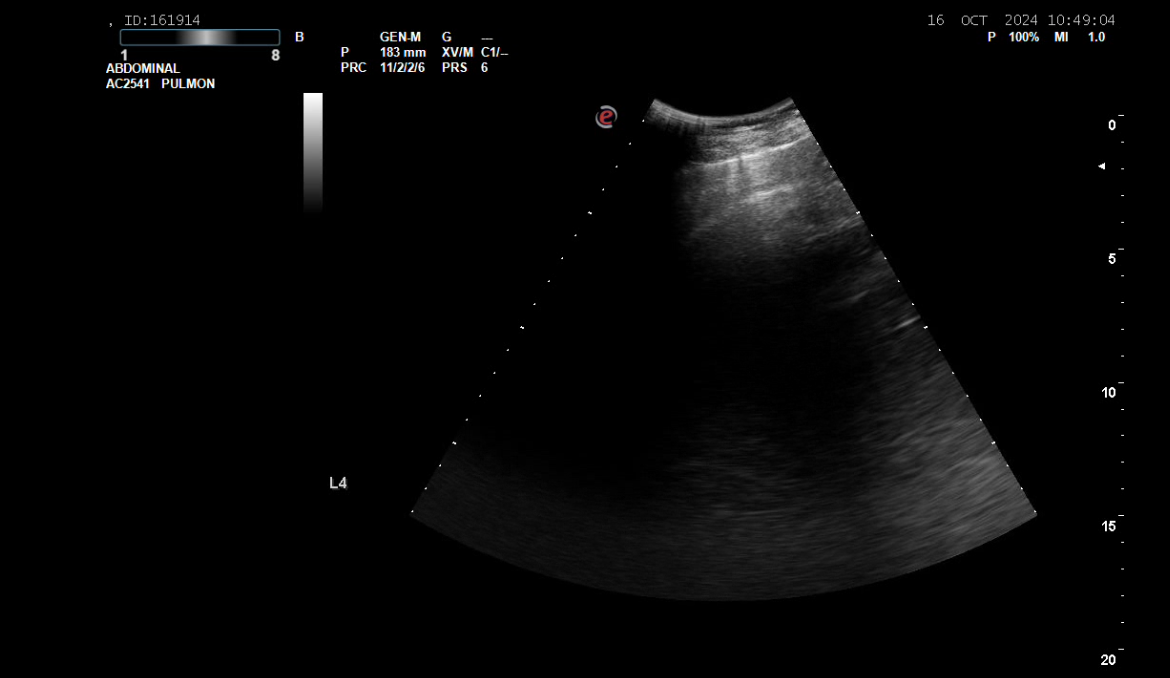

La eco a pié de cama muestra masa/atelectasia LID.

El uso de ecografía en Atención Primaria puede reducir tiempos de espera y permitir una derivación al dispositivo adecuado en base a la orientación diagnóstica.